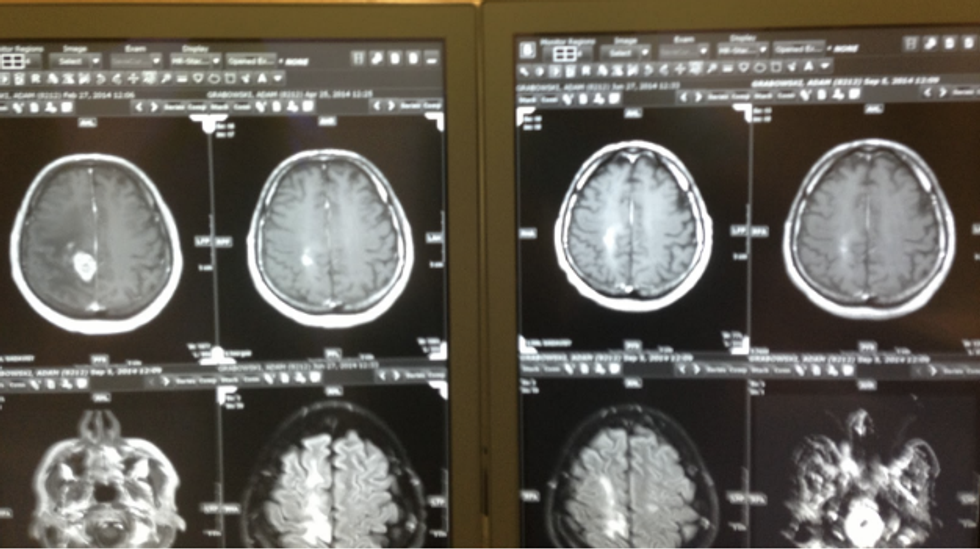

A 43-year-old male glioblastoma patient (which is a type of brain cancer) was asked what he thought of the cancer treatment in the United States to which he responded, “I would have never thought that the States would make it so difficult to treat a disease that is this serious. It is crazy to think about the number of people that are affected by this awful condition as well. The least the States could do is allow for more options, not just chemo and radiation.” He also later stated that the chemotherapy actually did more damage than good, stating that he felt far more weak and depressed rather than energized. His MRIs also showed little improvement as he was doing the suggested chemotherapy and radiation.

The MRI results above are from that same cancer patient that has been mentioned throughout. After his treatment in Germany, there was a significant change in the tumor. On the top left corner, one can see a significant white mass which makes up the tumor; but right next to that there is an MRI result that shows significant improvement after the vitamin infusion treatments done by Dr. Puttich. Although B17 has made a huge impact on many people all over the world, this type of alternative medicine is not the only type of its kind.